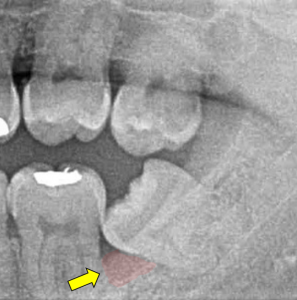

現代の人間は顎が小さく、親知らずが生えるための十分なスペースがないことが多いと言われてています。このため、親知らずが横向きに生えたり傾いて生えてきたりする場合があるのです。このような場合は歯ブラシが入りにくく、むし歯や歯肉炎・歯周炎の原因になってしまいます。

しかし、親知らずに歯茎が被っていたり、傾いていたり、位置が少しズレていたり、かみ合っていない場合は抜歯の対象となることが多いです。